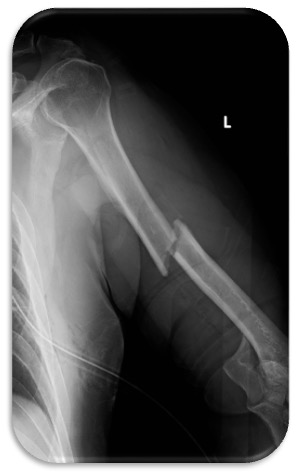

A fracture of the elbow bone, especially if accompanied by a dislocation, is a serious injury, as it requires treatment of both the fracture and possible damage to the ligaments and soft tissues. Elbow fractures can affect all three bones of the joint (radius, ulna, humerus) and are usually caused by severe traumatic stress. The patient usually presents with severe pain, swelling and restriction of movement, which lead to a visit to an Orthopaedic Surgeon. The diagnosis is confirmed by X-rays or other scans to accurately assess the lesion.

• Crushing fractures: Osteosynthesis with plates and screws or, in severe cases, replacement of the damaged parts.

Dr. Sahinis prefers the arthroscopic approach for simple fractures with two fragments, offering faster recovery and less pain. For more complex fractures, he applies open osteosynthesis or arthroplasty, focusing on anatomic reduction and internal fixation. Immediate elbow mobilization is essential to avoid postoperative stiffness.